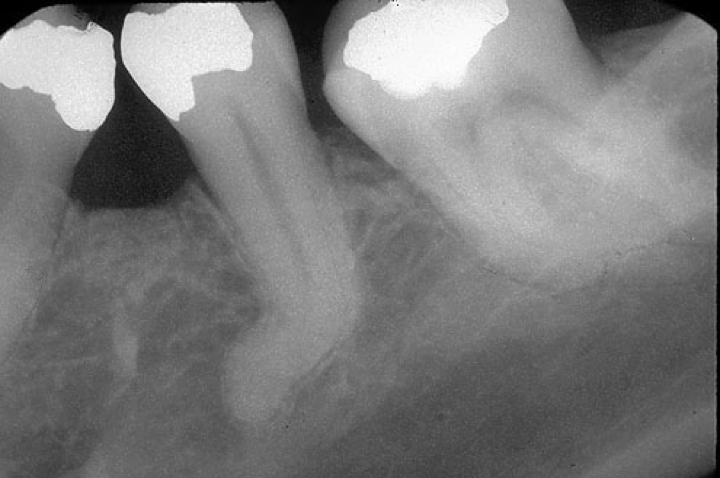

Taurodontisme : le taurodontisme est caractérisé par des dents dont la chambre pulpaire s’étend bien au delà du collet : il n’y a donc pas d’étranglement au collet, comme des dents d’herbivores.

Taurodontisme (quizlet.com).